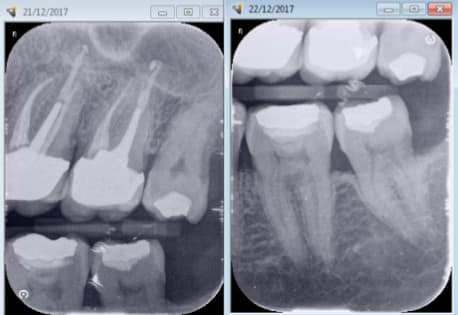

Capture d écran 2017 12 21 21.21 - Eugenol

Ba2be871 3220 4edb a5bc d126045cb763 jy2fsv - Eugenol

cyber ratiches

22/12/2017 à 08h04

Comment arrive tu à obtenir ces clichés ?

Capture d écran 2017 12 22 09.07 - Eugenol

chicot29

22/12/2017 à 09h18

Haut et bas sans modifier l'angulateur. Seulement la position du film. Ici taille 2.